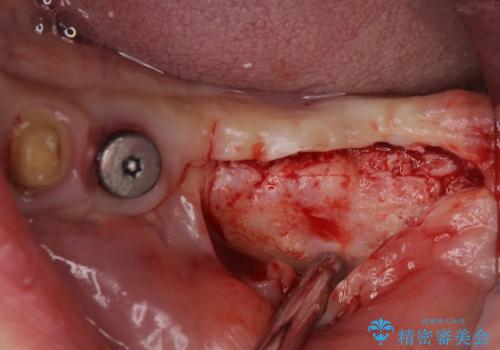

左右ともに歯根が破折しており、抜歯が必要であったため、抜歯後にインプラント補綴治療を行うこととしました。

左側は骨欠損が著しいことが予想されるため、骨造成術並びに歯肉移植術を併用することとしました。

仮歯がない状態を極力避けたいとのことで、外科処置を少しずつ進めていくことになり、治療期間は2年間を要しました。